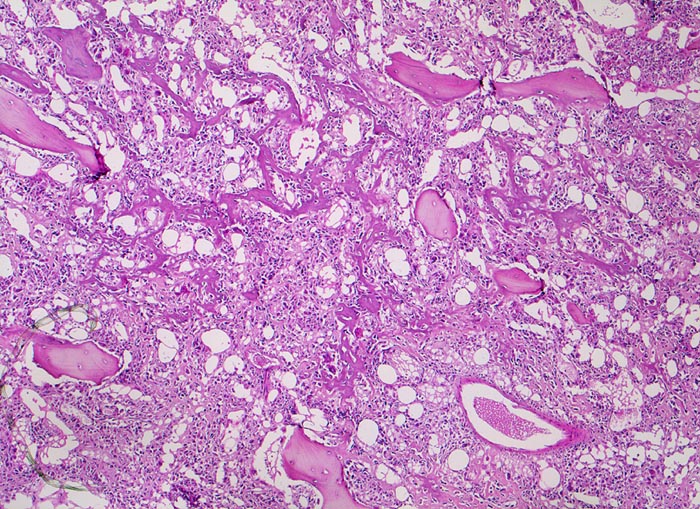

• Tibiametaphyse mit angrenzendem Weichteilgewebe.

• Das Sarkom infiltriert diffus den spongiösen Knochen der Diaphyse und hat präexistente Knochenbälkchen verdrängt.

• Der Tumor hat die Korticalis destruiert und infiltriert die angrenzende Skelettmuskulatur.

• Der Tumor besteht aus neugebildetem bereits verkalktem Knochen oder einem Netzwerk von primitiven Osteoidtrabekeln. Entlang oder innerhalb der Osteoidtrabekel lokalisierte polymorphe Tumorzellen mit ausgeprägten Kernatypien und zahlreichen Mitosen. Leicht verwaschene Kernstrukturen als Folge der Gewebsentkalkung.